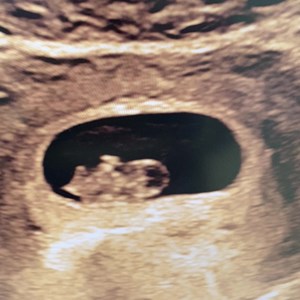

Det lille spirende liv uge 8 💓 Det lille fine fosteranlæg her er bare 17,5 mm lang. Det ...

TIDLIG TERMIN-SCANNING 👀🫶🏼🫧 Skal du/I til tidlig scanning i graviditetens første tri...